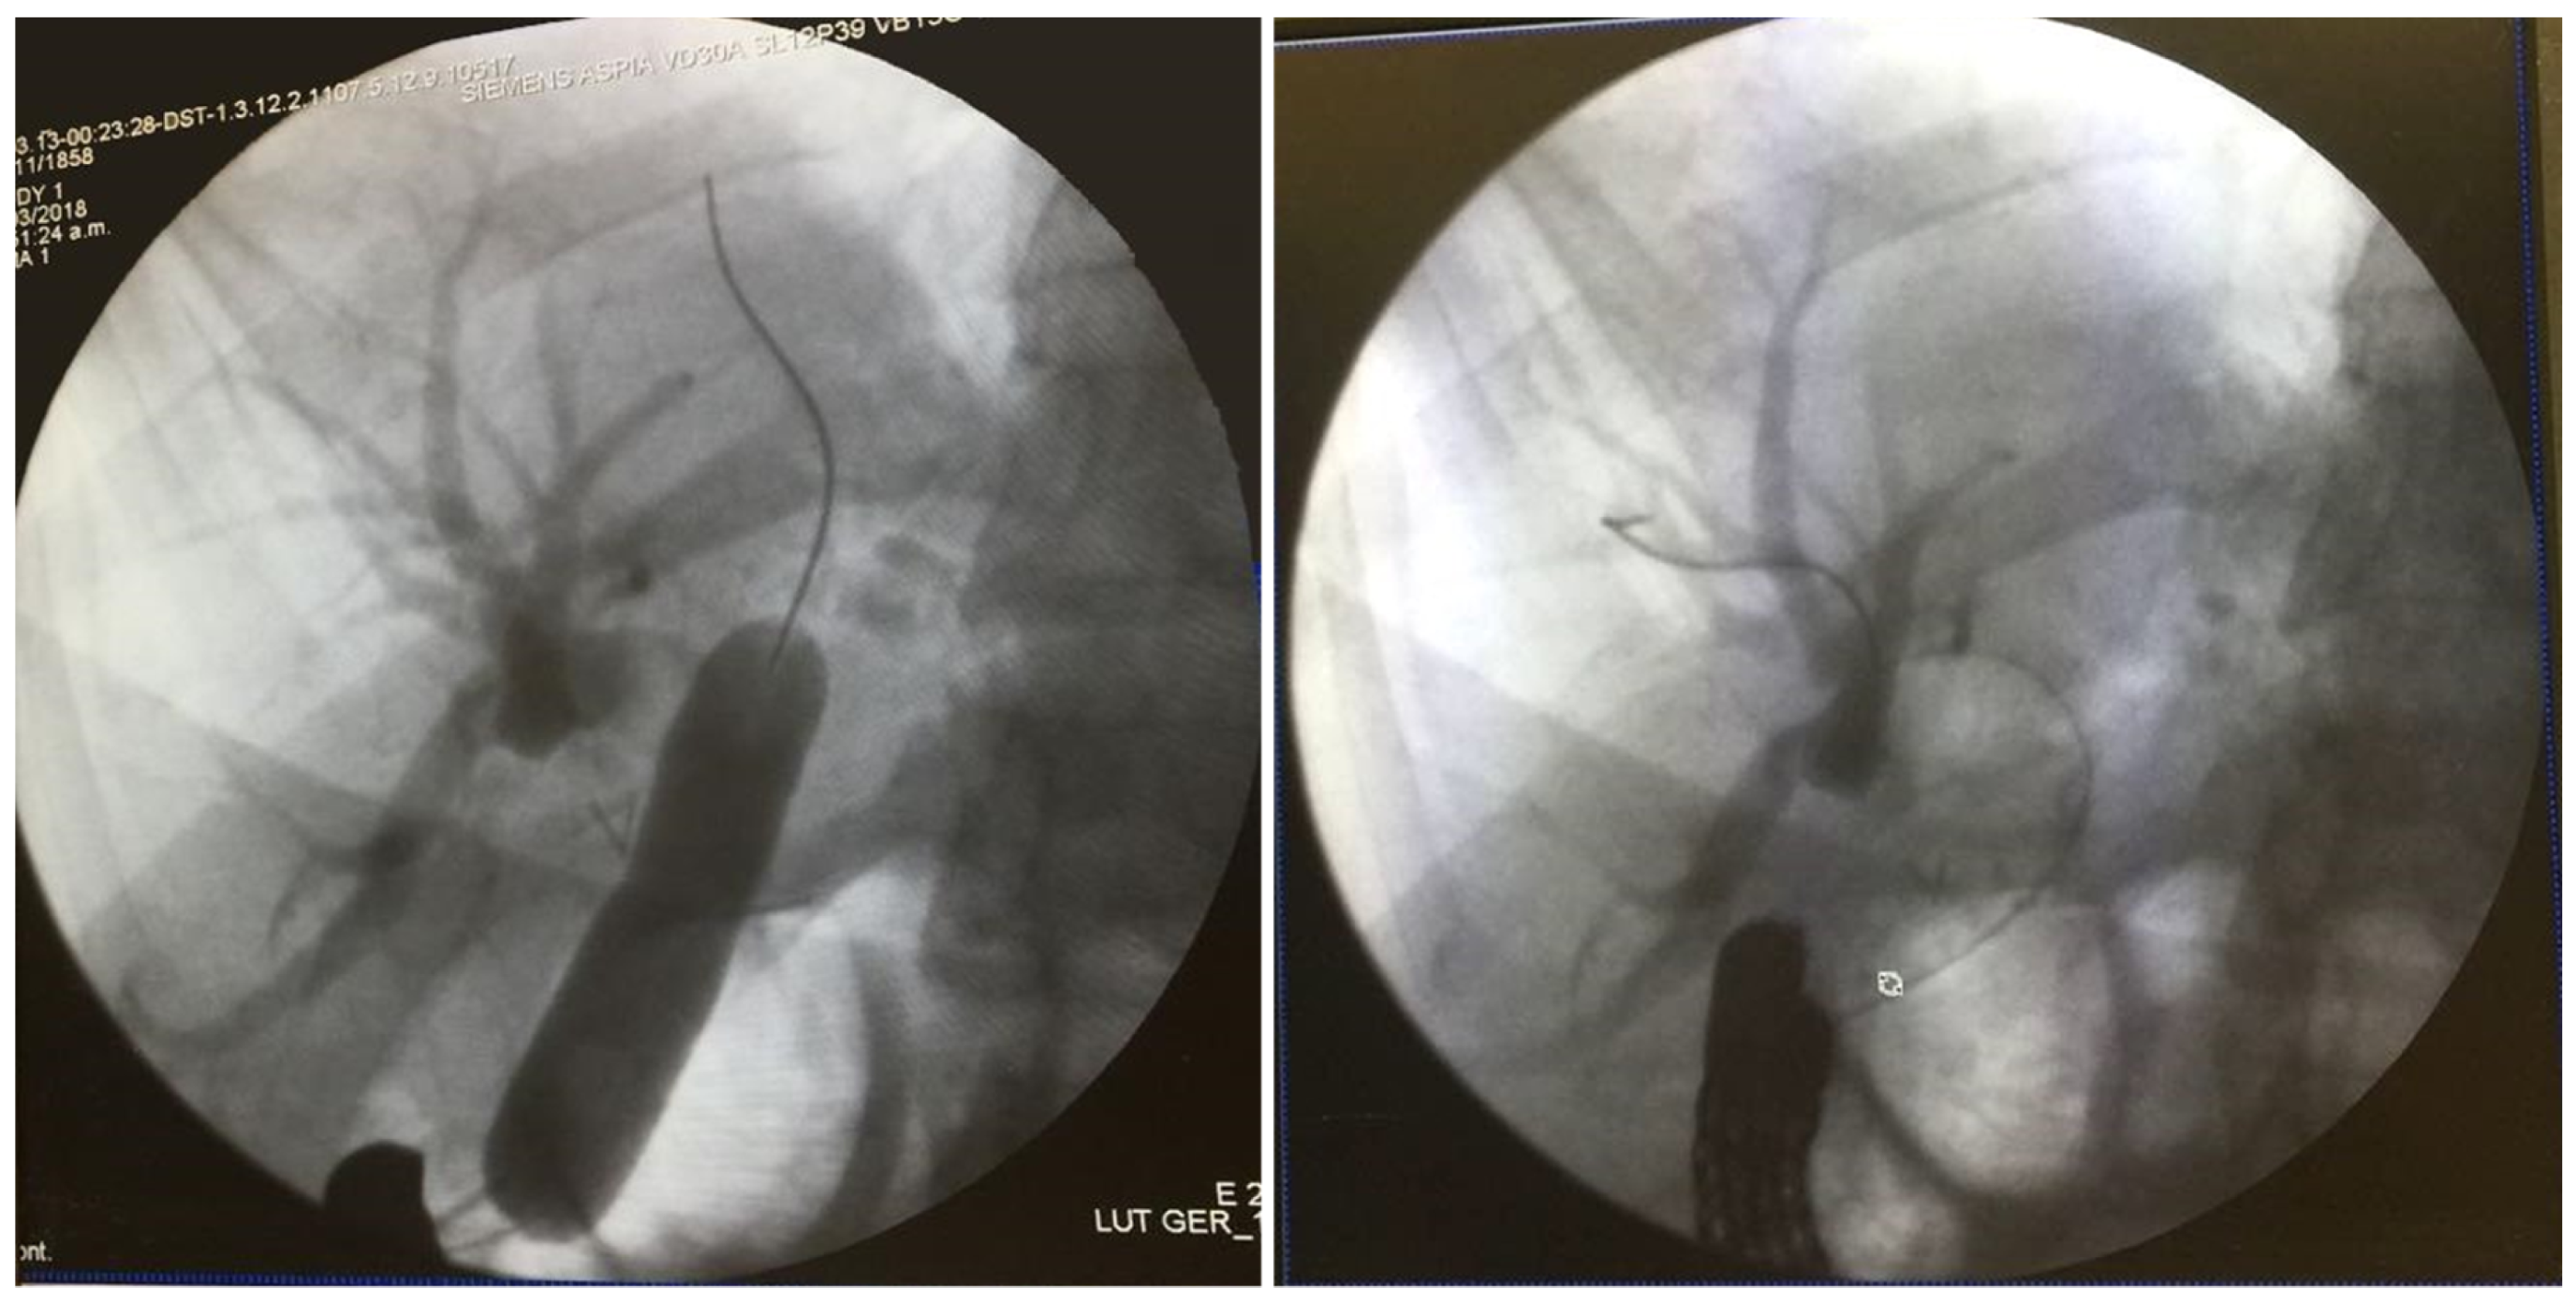

A standard side-viewing endoscope (Olympus TJF 160 VR or TJF 145, Tokyo, Japan) was advanced through the jejunal trocar in caudocephalad direction until the papilla was visualized. Once successful catheterization of the papilla was obtained, ERCP was carried out in a standard fashion showing a filling defect in the common hepatic duct proximal to the anastomosis. Balloon dilation of the anastomosis was required (Figure 3). A single 5 mm stone and biliary sludge were removed with a retrieval balloon catheter. Subsequent cholangiography showed no evidence of filling defect. The enterotomy was closed with continuous sutures in double layer (Figure 4). There were no incidents during the surgical procedure.

Figure 3.

ERCP showing balloon dilation of bilioenteric anastomosis and intrahepatic biliary ducts.